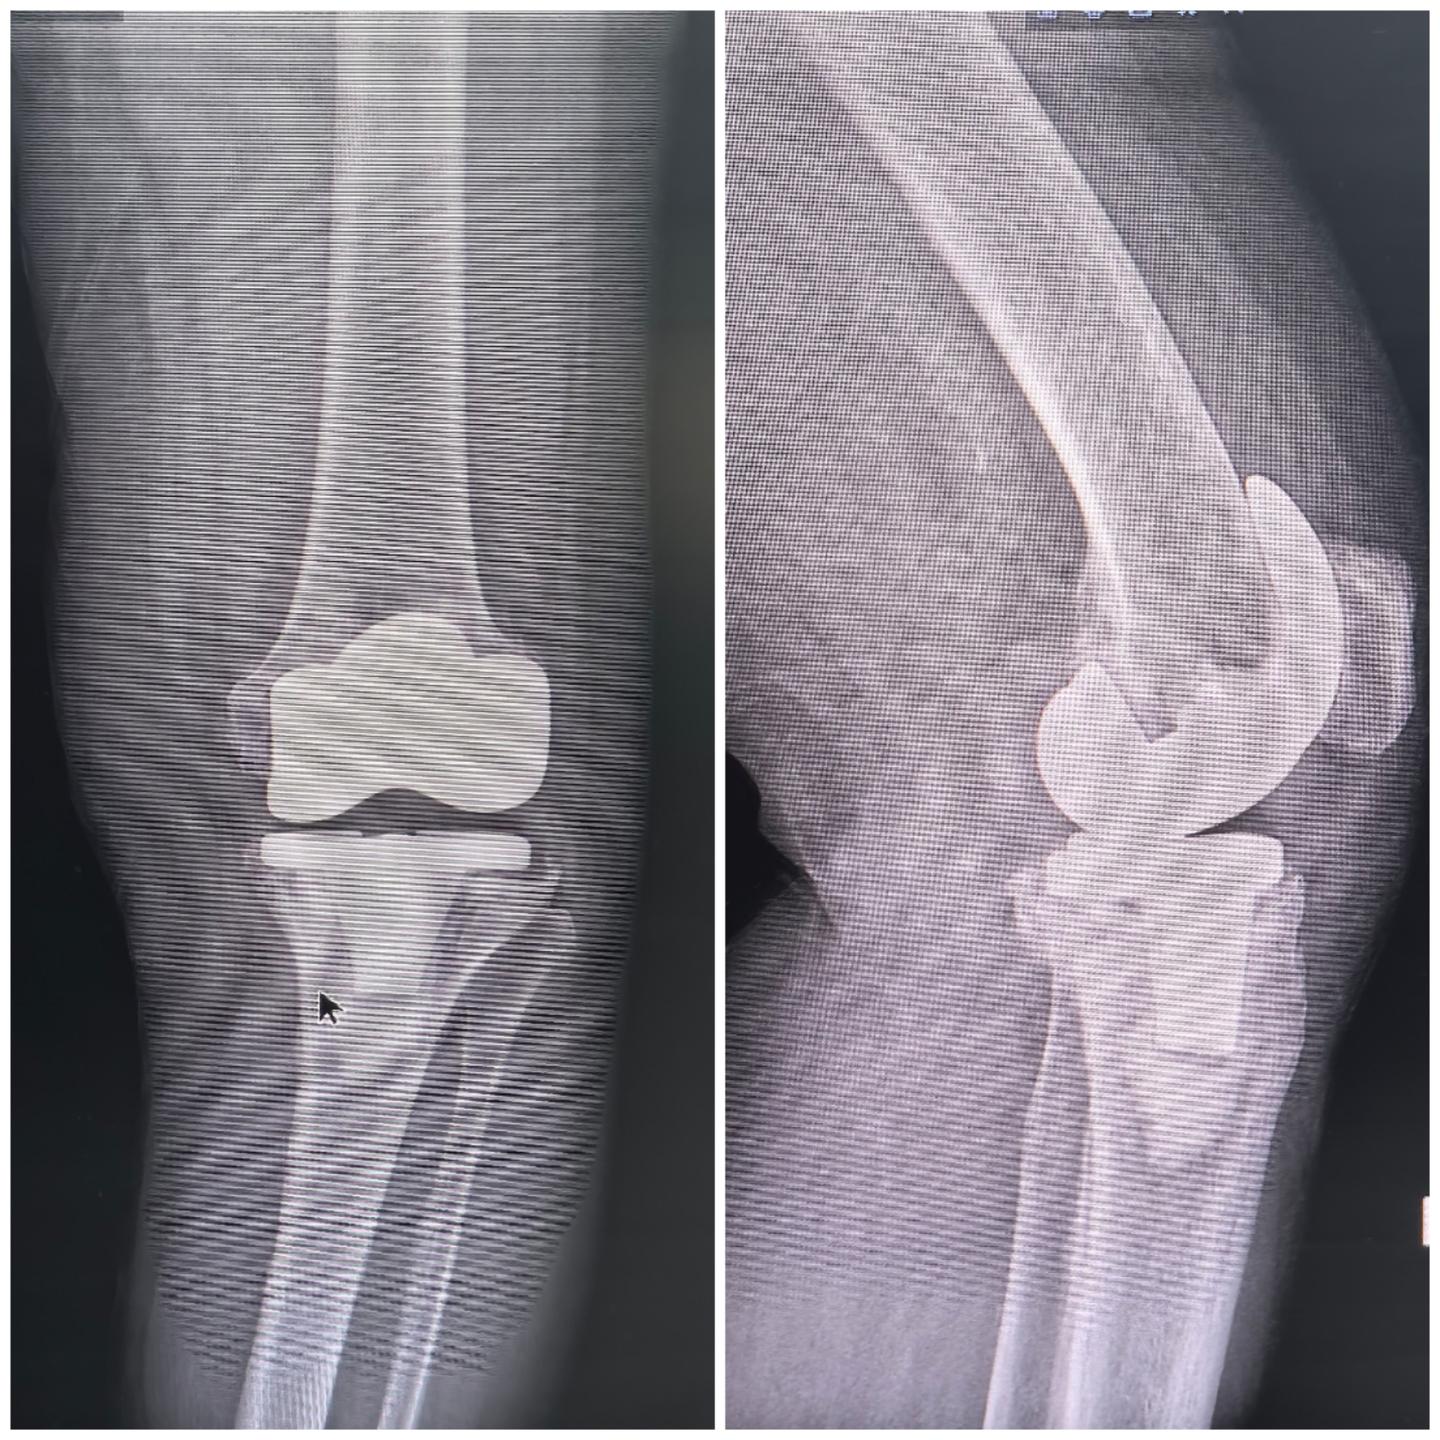

膝关节翻修。初次膝关节置换术后17年,80岁高龄,顺利翻修,希望再次延续20年,活到一百岁🌹完美🌹